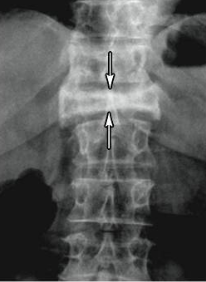

compression fracture